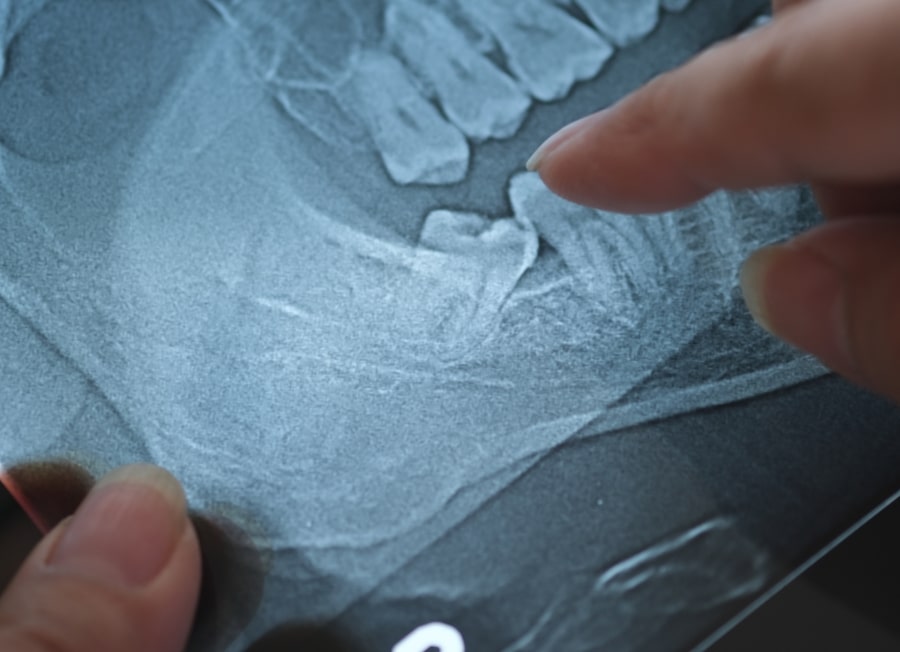

• Surgical dental extraction

Required for impacted, broken, or partially erupted teeth. This procedure may involve a small incision and removal of bone.